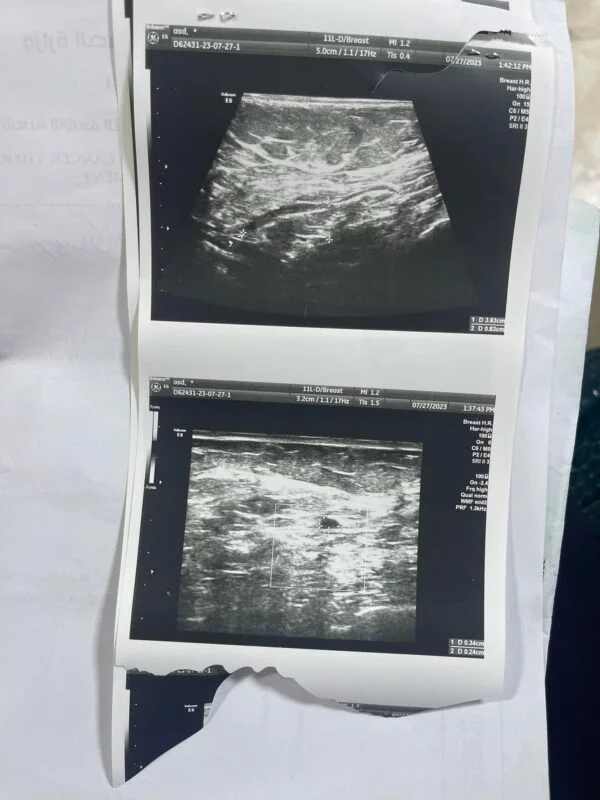

الحالة الإنسانية (8): امرأة تحتاج علاج لسرطان الثدي

أنا مريضة بسرطان الثدي، أعاني من صراع صحي صعب، وأجد نفسي في موقف مالي صعب حيث ليس لدي المبلغ اللازم للعلاج والرعاية اللازمة، وزوجي مريض وعاطل عن العمل، وليس لنا معيل.

تم اخذ المريضة الى الطبيب المختص واخبرنا ان هناك ورم بسيط في الثدي الاخر وان شاء الله يمكن ان يختفي بالعلاج لكن يجب ان تستمر على العلاج دون انقطاع نهائيا لضمان عدم رجوع المرض او انتشاره في اماكن اخرى. وبحمد الله وفضله تم تأمين وتسليم المريضة الدواء الذي تحتاجه لمدة شهر.